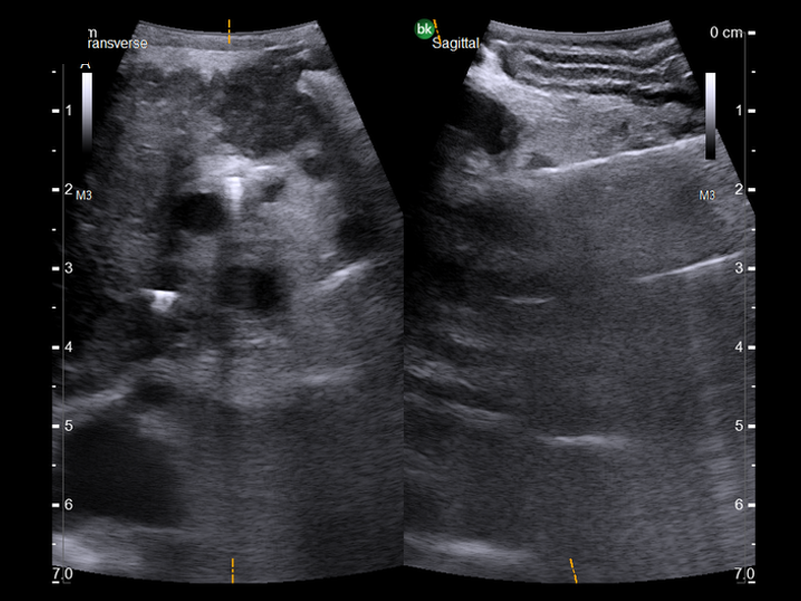

- Monitor Progress: Compare live images with previous scans simultaneously using Dual Live Compare and Picture in Picture modes.